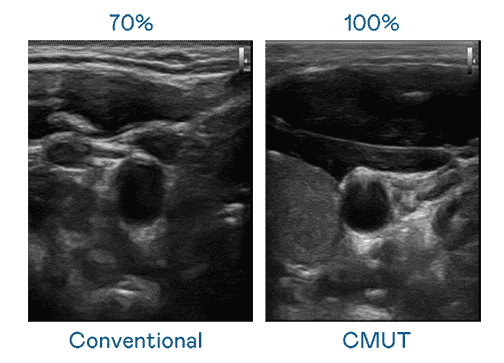

CMUT 技术是一种用电容式微机电元件来产生超音波讯号的技术。。与传统 PZT 压电式技术相比,,,,CMUT 频宽增加 30%,,更宽频的超音波讯号让影像解析度大幅提升,,,,是实现高影像品质医疗超音波扫描、、促进精准医疗发展的关键技术。。。。

大频宽带来超清晰影像

超音波影像的解析度高低,,,,首先取决于探头能发出的讯号频宽。。人生就是博 CMUT 可提供高清晰的超音波讯号,,,,提供高频宽、、高灵敏度、、影像纹理细节更高的超音波影像,,协助医护人员缩短影像判读时间及利用精准的医疗影像进行诊断。。。